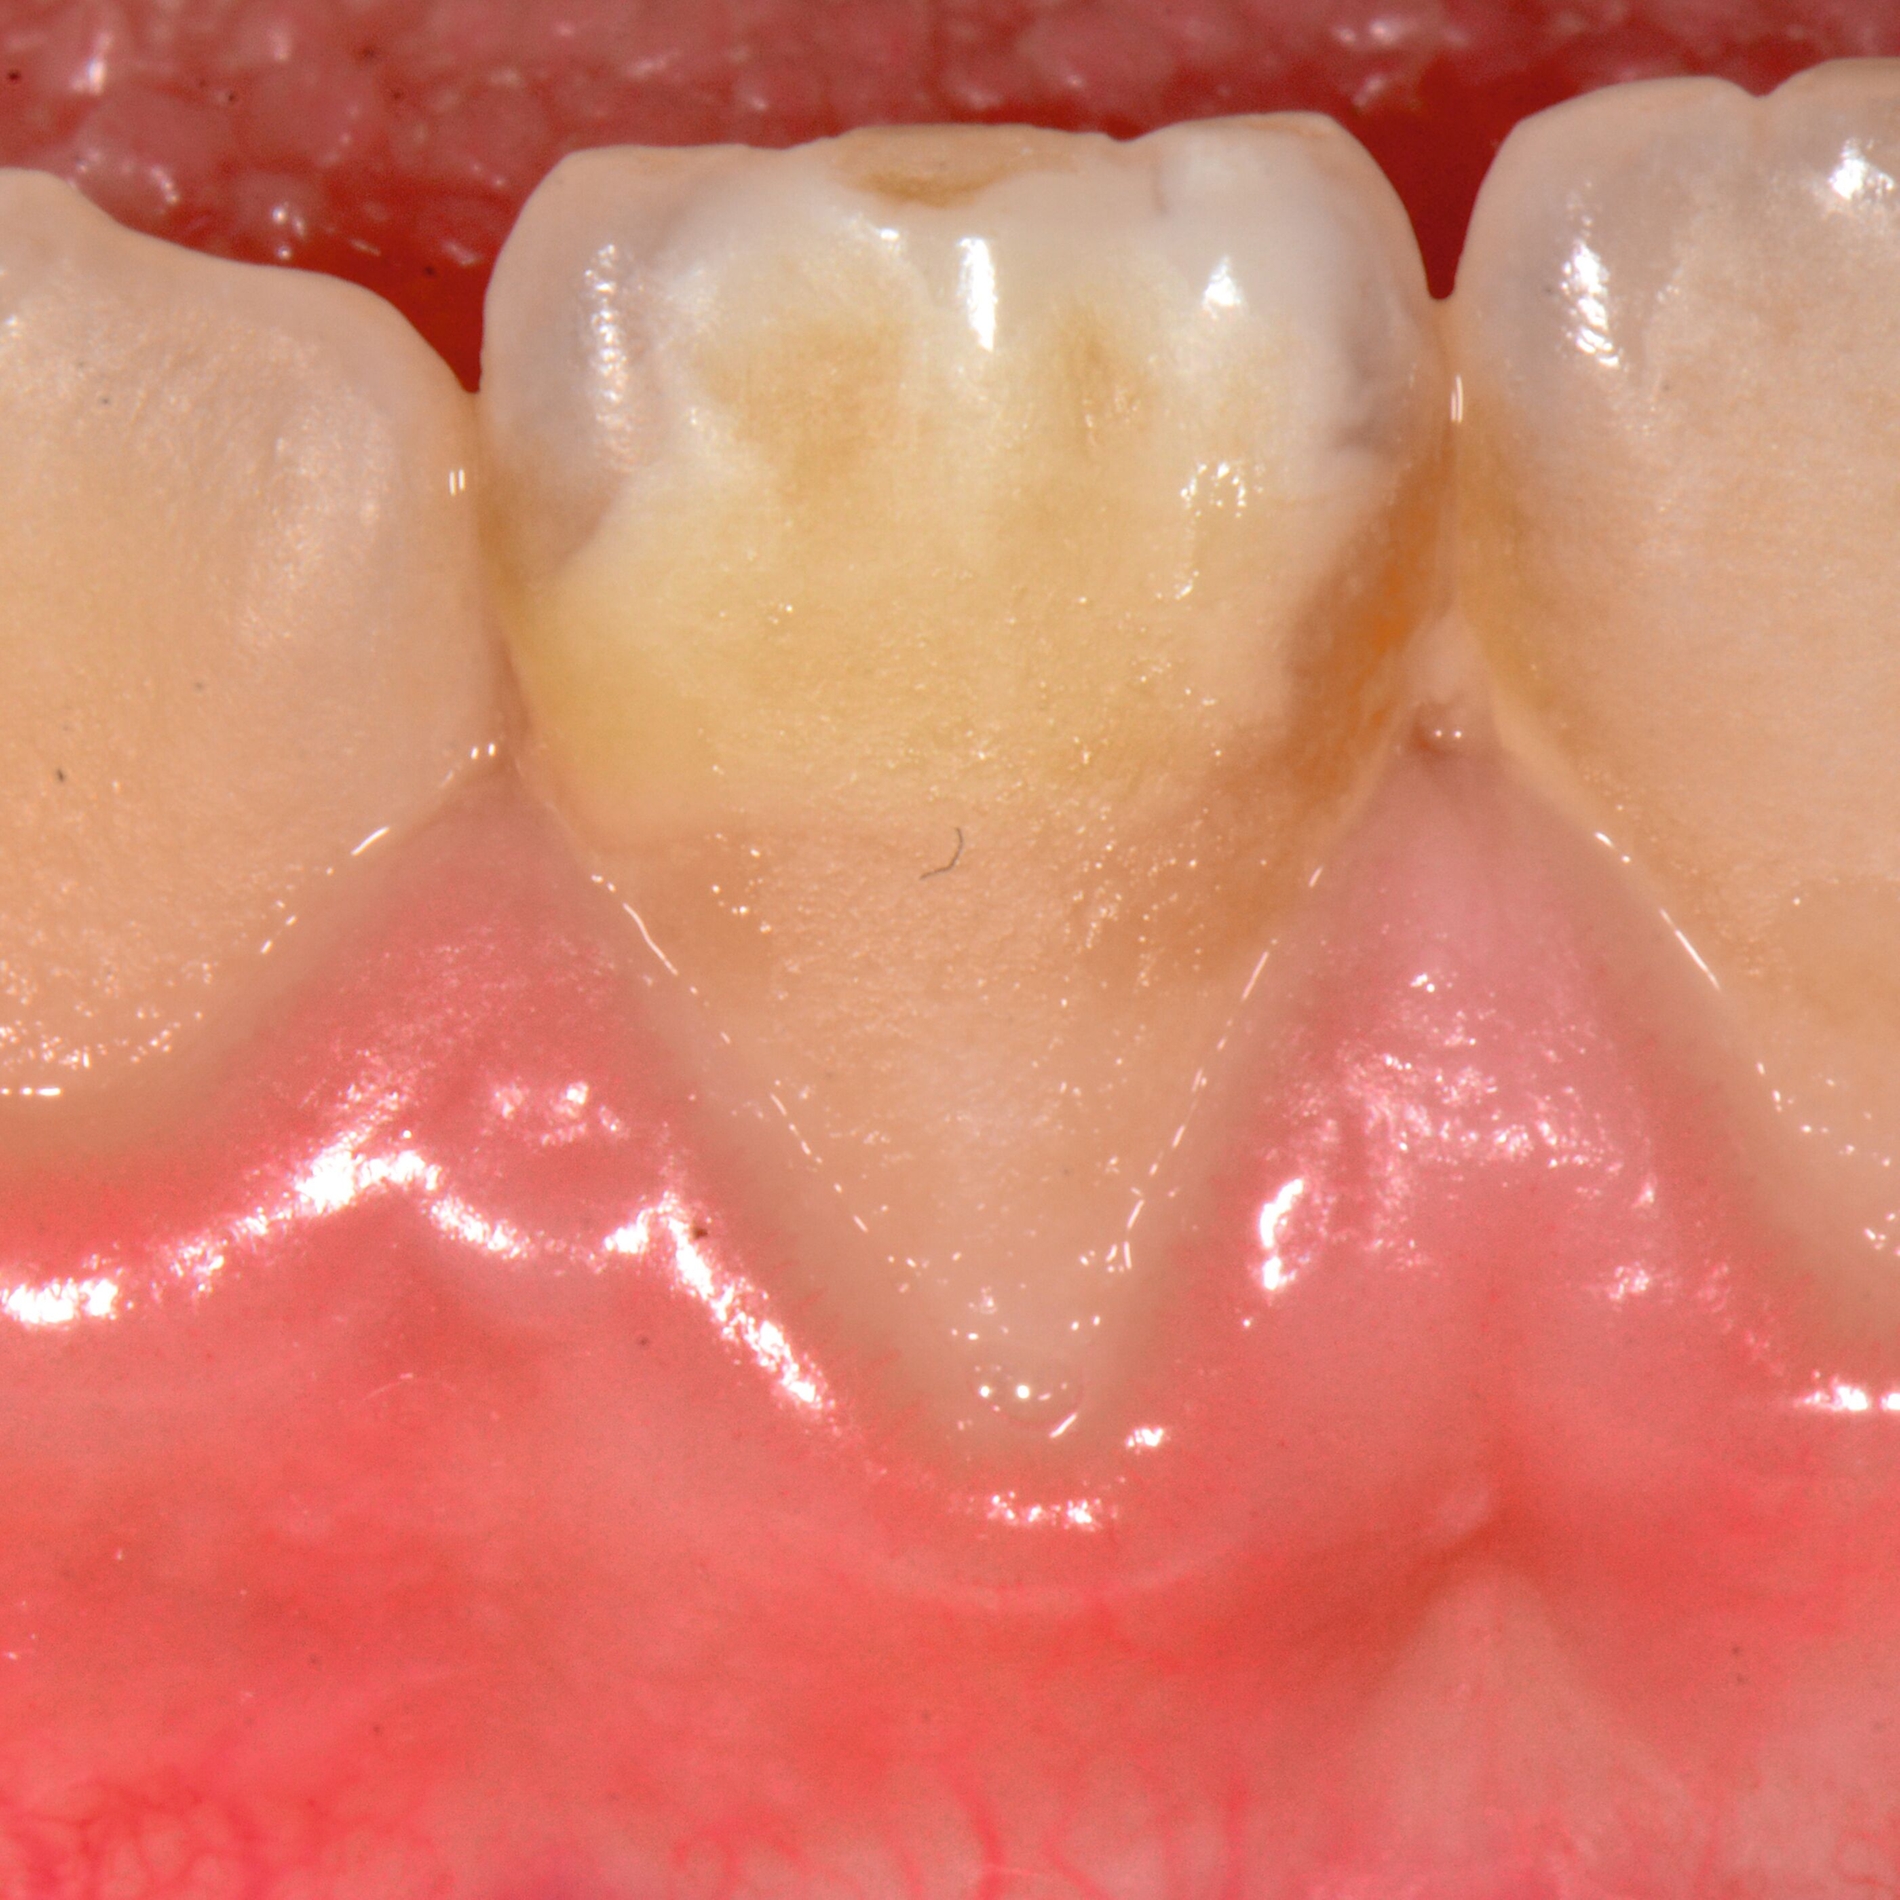

Bei post- beziehungsweise präeruptiven Oberflächendefekten ergibt sich in einigen Fällen die Indikation zur Restauration dieser MIH-Zähne. Unter Verweis auf die Lokalisation von MIH-bedingten Hypomineralisationen außerhalb der typischen Kariesprädilektionsstellen – zum Beispiel okklusale Fissuren und Grübchen oder Approximalflächen – werden diese als „atypische Restaurationen“ (engl.: „atypical restoration“, Abbildung 6) klassifiziert. Als ein weiteres Erkennungsmerkmal gilt die Präsenz von Hypomineralisationen im Bereich der Restaurationsränder. MIH- und kariesbedingte Restaurationen können und sollten sicher voneinander abgegrenzt werden.

Für die Dokumentation und Klassifikation der MIH wurden verschiedene Systeme vorgeschlagen. Als historisch und veraltet gilt der (modifizierte) DDE-Index. Demgegenüber haben die Kriterien der EAPD – abgegrenzte Opazitäten (Abbildung 3 und 4), Schmelzeinbrüche (Abbildung 5), atypische Restaurationen (Abbildung 6) – mittlerweile die weiteste Verbreitung gefunden. Diese wurden 2003 erstmals zur Beschreibung der MIH auf empirischer Basis publiziert [Weerheijm et al., 2003] und den Jahren 2010 und 2022 im Rahmen der damaligen MIH-Workshops bestätigt [Lygidakis et al., 2010; 2022].